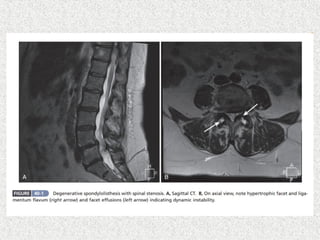

 LS spineX-ray  AP  Lat  Lat flexion/extension  Oblique if suspecting spondylolysis  MRI  SPECT  HRCT

 Instrumented posterolateralfusion(wiltse & spencer)  No significant neurological symptom  Good spinal alignment  Sufficient surface area >2cm2 of transverse process  Less surface area for posterolateral fusion  Posterior only approach with circumferential fusion(posteior/transforaminal lumbar interbody fusion PLIF/TLIF)  Ant lumbar interbody fusion with post supplemental fixation  Used if small transverse process  Salvage procedure if non union in posterolateral fusion  Patients with neurological symptom  Direct/indirect decompression also needed